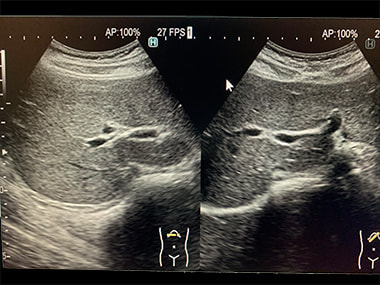

腹部エコー検査:

腹部臓器(肝臓・胆のう・膵臓・腎臓・脾臓)、腹部大血管、骨盤病変(膀胱・前立腺・子宮・卵巣)、リンパ節などに異常病変がないかを検査します。